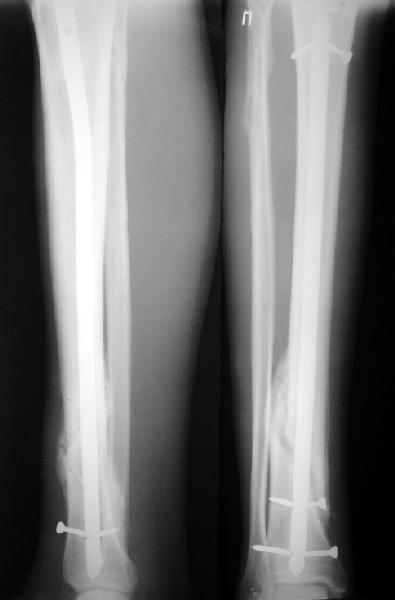

На мой взгляд, на снимках, приведённых Вами - неправильно сростающийся перелом дистальной трети большеберцовой кости, состояние после остеосинтеза интрамедуллярным гвоздём.

Как Вы пишите снимок под номером 1 - менсяц после операции, под номером 2- два месяца после операции.

Вы не послали послеоперационный снимок, поэтому трудно судить о состоянии редукции после операции.

I think that the X-Rays show S/P IMN of Spiral # of the Distal Tibia consoles in misalignment.

You wrote that a picture number 1 - f month after the surgery, and number 2-two months after the surgery.

You have not sent a postoperative X-Rays; so it's impossible to discuss about the condition of a reduction after operation.

Let to express concerning technique of operation my opinion... Insertion of a screw to medial side of a nail in distal fragment would help you to reduction and to keep this fracture in anatomic position has prevented varus deformity and displacement on width. By the way, if it is possible send a postoperative picture.